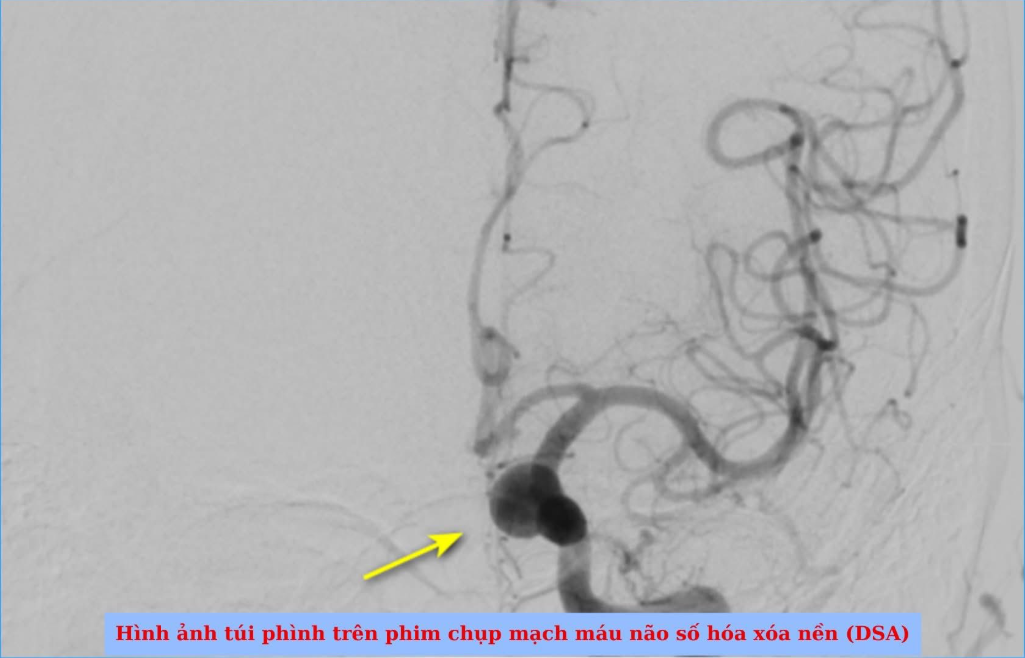

Nữ bệnh nhân tên N.T.Q, 50 tuổi, ngụ tại phường Thủ Đức, TP HCM tình cờ phát hiện túi phình động mạch cảnh trong đoạn mấu giường khi đi khám sức khỏe định kỳ. Kết quả chụp MRI 3T cho thấy túi phình có kích thước 10 x 8 mm, cổ túi phình rộng 6 mm – một trường hợp được đánh giá là có túi phình khá lớn.

Sau khi hội chẩn kỹ lưỡng, đội ngũ y bác sĩ quyết định áp dụng phương pháp đặt stent chuyển dòng. Đây được xác định là lựa chọn phù hợp nhất cho trường hợp của bệnh nhân, vừa đảm bảo hiệu quả điều trị lâu dài, vừa hạn chế tối đa sự xâm lấn.